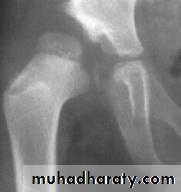

Imaging1. U/S in the neonatal period. Should done for every child at risk and every hip with sign of instability2. X-ray signs In neonate → Von rosens line In infancy → Shentons line Perkins line Acetabular roof angle Smal epiphysis In child hood → false acetabulum3. Arthrography